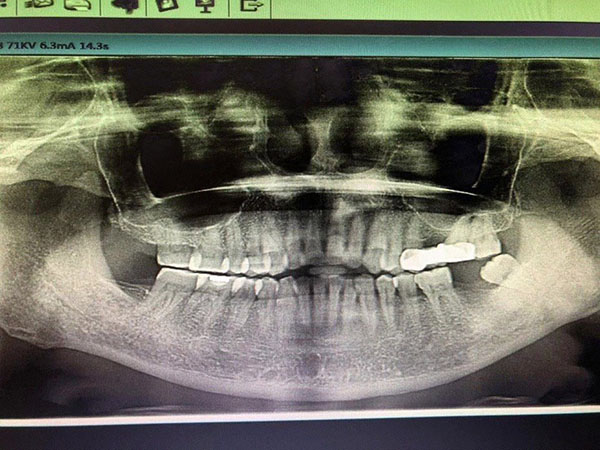

種植牙牙片